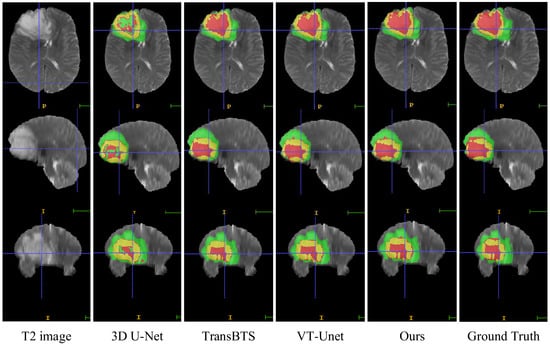

4.8. Visual Comparison

In this section, we compare the visualization of the brain tumor segmentation results between the proposed method and 3DU-Net, TransBTS, and VTU-Net, as shown in Figure 4. In Figure 6, the first row is the cross-sectional image of the brain tumor, the second row is the sagittal image, and the third row is the coronal image. For the convenience of observation, we show all three cross-sectional images and set the coordinates of the intercept point as (109, 89, 78). The red label in the figure represents the ET area, the yellow label represents the TC area, and the green label represents the WT area. It can be seen from Figure 6 that all models have the best segmentation effect for the WT region, and the segmentation effect for the two complex edges of ET and TC is very different. Compared with Ground Truth, our model is more accurate for the segmentation results of edge details.

Figure 6. Visual comparison of MRI image segmentation results.